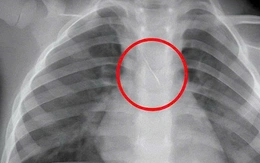

Kim chọc tủy dài 22mm rơi vào đường thở bé trai 3 tuổi khi làm răng

Bé trai nhập viện trong tình trạng ho sặc dữ dội, được xác định hóc kim chọc tủy dài 22mm rơi vào đường thở khi đang làm răng.